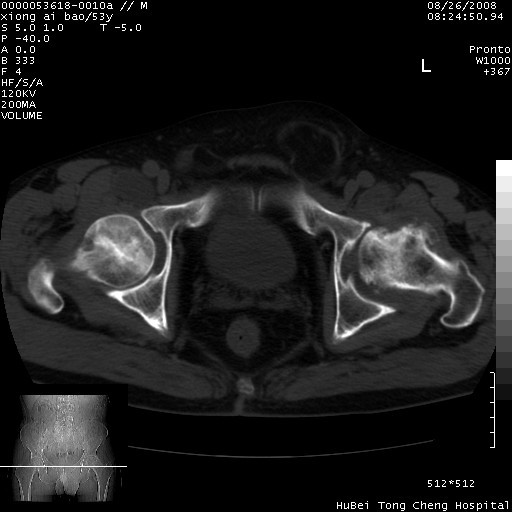

标题: CT15583:M,53Y。请老师指教分析骨盆及其他病变。 [打印本页]

标题: CT15583:M,53Y。请老师指教分析骨盆及其他病变。

股骨头坏死/腹股沟疝。

双侧股骨头无菌坏死,左侧腹股沟斜疝。

非常典型病例,双侧股骨头坏死伴双髋关节周围软组织肿胀,左腹股沟疝。

双侧股骨头坏死伴双髋关节周围软组织肿胀,左腹股沟疝。

双侧骨股头无菌性坏死,左侧腹股沟疝

双侧髋关节肿胀明显,感觉还不能排除结核。

考虑双侧髋关节结核,左侧腹股沟疝